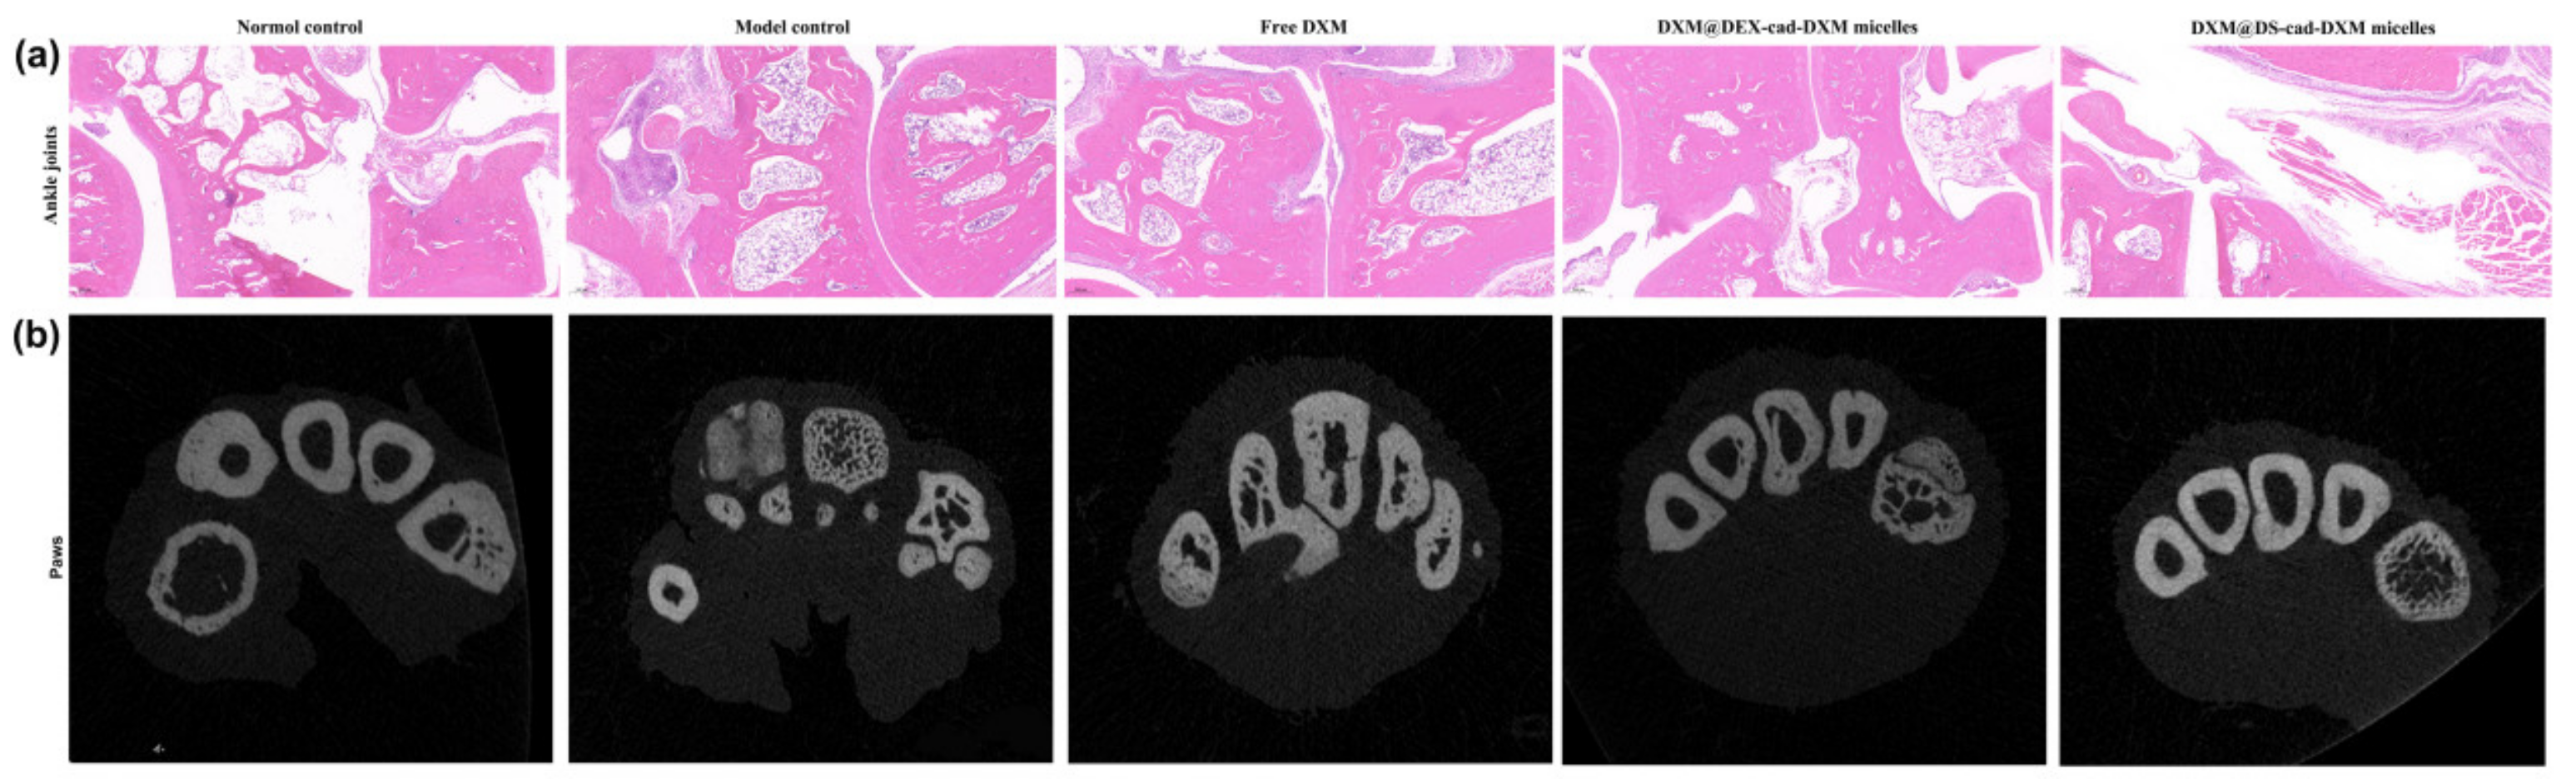

2.6. Therapeutic Efficacy of AIA Models

2.7. Safety Evaluation In Vivo

3.10. In Vivo Therapeutic Efficacy of DXM@DS-cad-DXM

3.11. Safety Evaluation DXM@DS-cad-DXM